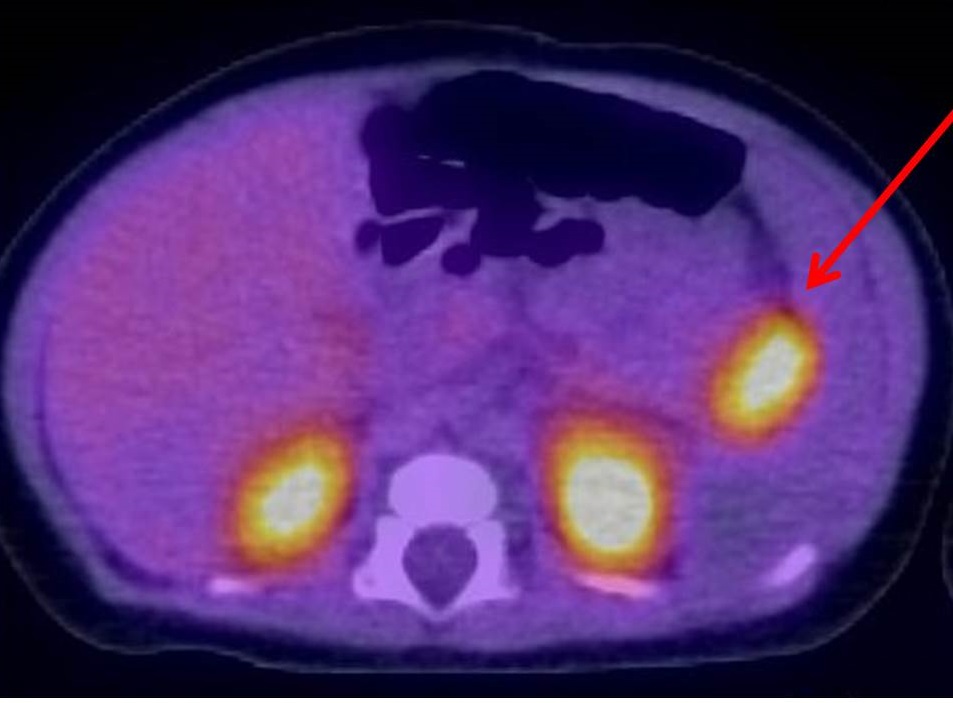

该患儿经18F-多巴PET成像技术检查发现胰腺尾部存在局造型病灶,外科董岿然教授亲自主刀,采用腹腔镜微创顺利切除了胰腺的病灶部位,患儿术后血糖即恢复,正常饮食即能维持正常血糖,无需再用任何药物和额外的葡萄糖补液治疗,经过医院慎重观察多日后血糖稳定顺利出院,患儿告别了天天躺病床上接受高流量静脉补液的痛苦经历。